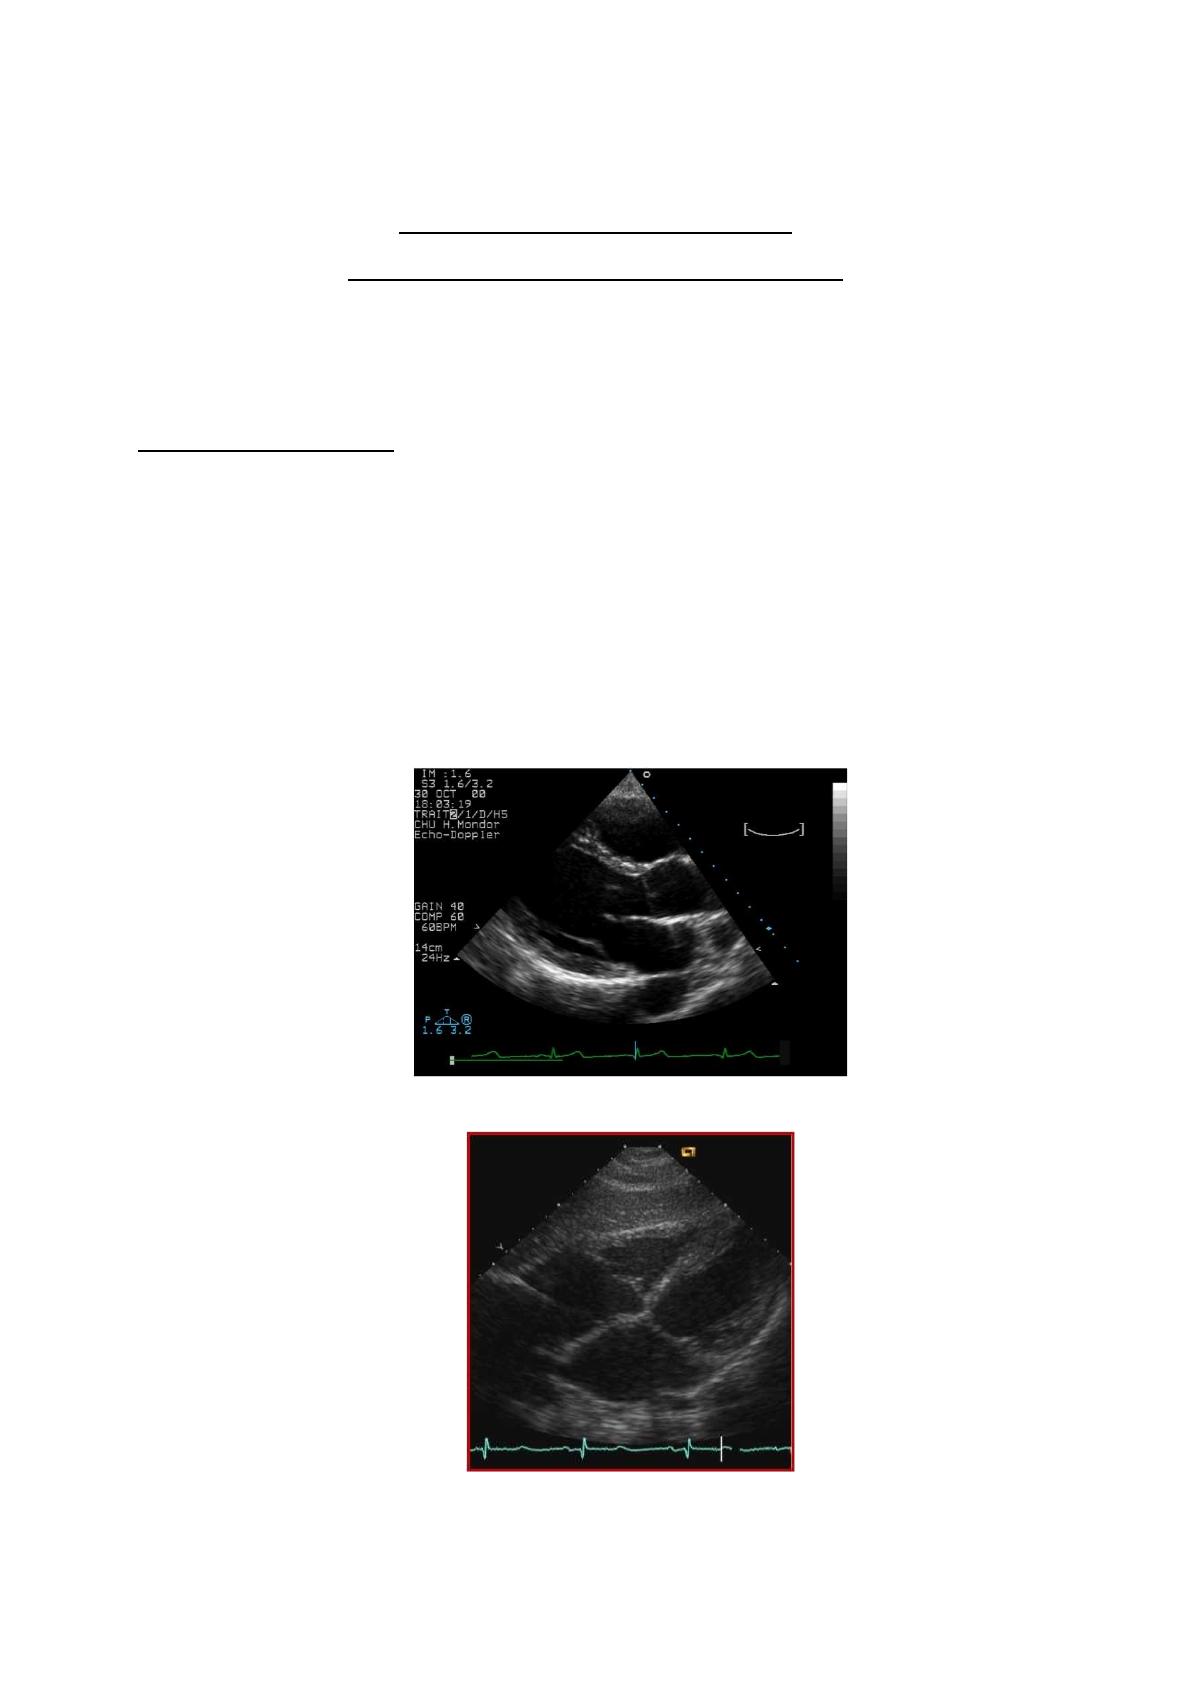

- Cas clinique n°1 :

Vous recevez une patiente de 56 ans pour fièvre trainante depuis 48H00, asthénie et

douleur épigastrique depuis ce soir.

Elle n’a pas d’ATCD particulier, aucune intervention chirurgicale, et traitée par Lévothyrox

25 :1cp le matin.

À l’examen, la température est à 38, 2°C, la PAS à 135 mmHg, PAD 85 mmHg, le pouls à

100/min.

L’interrogatoire ne retrouve rien en dehors de cette douleur épigastrique.

L’auscultation cardio-pulmonaire est sans grande particularité, si ce n’est une diminution

du murmure vésiculaire aux deux bases que vous mettez sur le compte de la douleur. La

percussion thoracique déclenche une petite douleur sous scapulaire droite. La palpation

abdominale retrouve une sensibilité épigastrique et de l’hypochondre droit, sans défense ni

contracture.

- A/ Comment complétez-vous votre examen clinique avec l’échographie ?

- B/ Vous découvrez un petit épanchement pleural droit, quels sont les signes

échographiques d’une pneumopathie de la base droite avec un petit épanchement ?